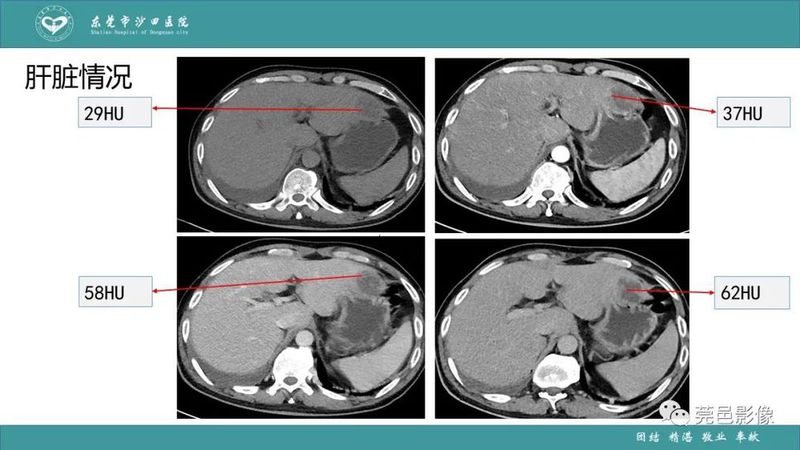

「肺炎克雷伯杆菌肺炎」影像学诊断+鉴别诊断